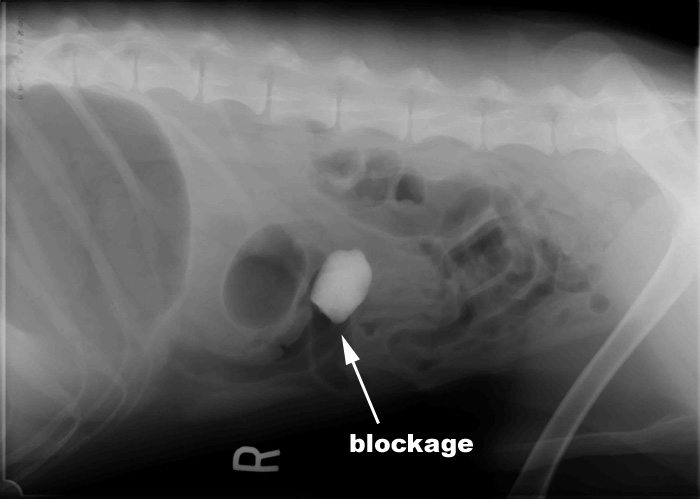

James' abdomen: in the middle you can see the rock in his intestines.  He is also gassy behind the obstruction.